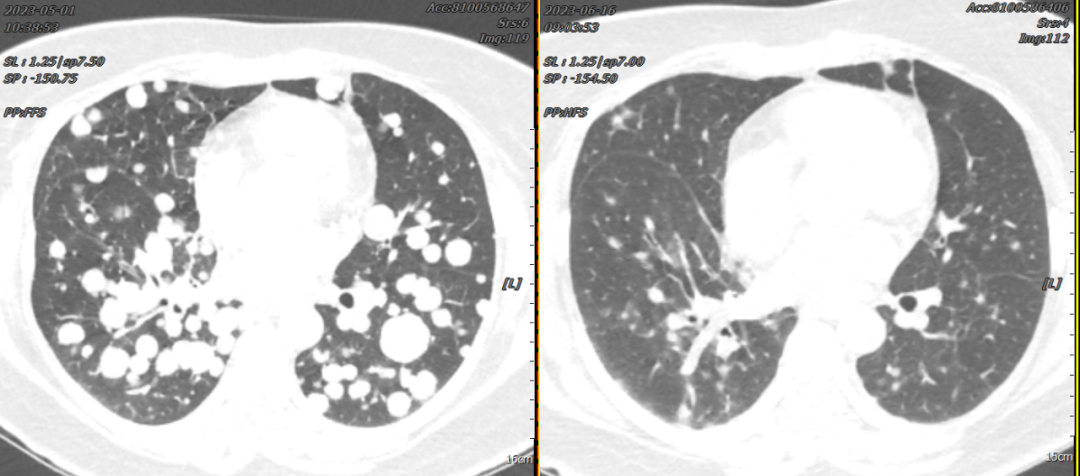

Patient Song XX, female, 41 years old, presented with cough, expectoration, accompanied by chest tightness and shortness of breath. In May 2023, a chest CT scan performed at our hospital revealed a mass near the hilum of the right upper lobe with diffuse multiple nodules distributed in both lungs, stenosis and occlusion of the right upper lobe bronchus, and encasement of the right upper pulmonary artery and brachiocephalic veins, suggesting right lung cancer with bilateral lung metastases. Subsequently, a CT-guided lung biopsy was performed, and pathological examination confirmed right lung invasive adenocarcinoma. Genetic testing showed an EGFR-19Del mutation. The diagnosis was "right lung adenocarcinoma, driver gene-positive (EGFR-19Del mutation)." After oral targeted therapy, the patient's cough, chest tightness, and shortness of breath significantly improved. A follow-up chest CT one month later showed significant shrinkage of the lung lesions, with most tumors gradually disappearing. The clinical efficacy was evaluated as PR (Partial Response).